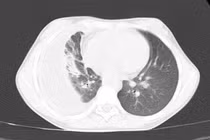

Khó thở, tức ngực bệnh nhi 13 tuổi tràn khí màng phổi do vỡ kén khí

Kén khí lớn làm giảm khả năng trao đổi khí và gây khó thở. Khi kén khí vỡ, người bệnh có thể bị tràn khí màng phổi, dẫn đến xẹp phổi, suy hô hấp cấp.

Kén khí phổi là một dạng tổn thương phế nang, đây là tình trạng trong nhu mô phổi hình thành những túi khí hoặc khoang chứa khí bất thường.